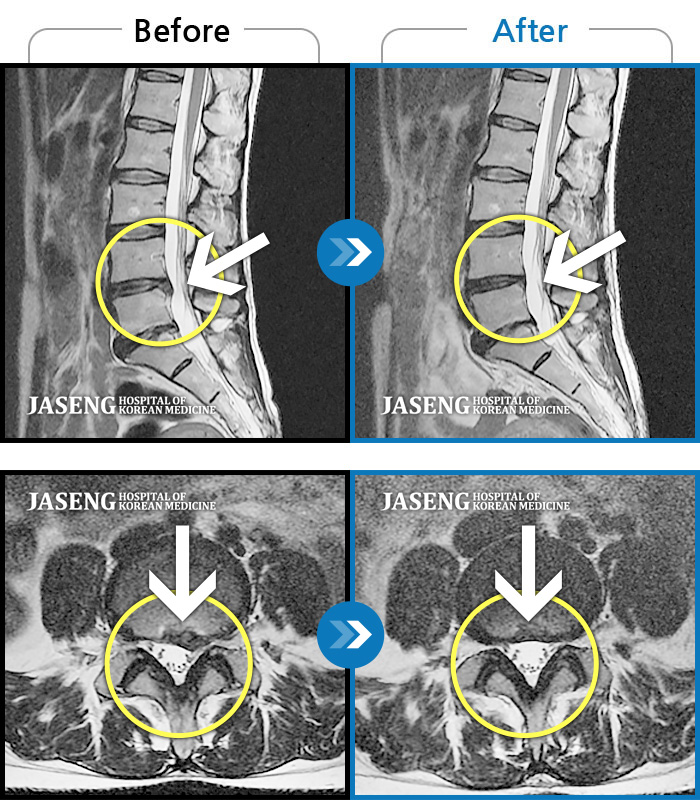

Before

After

환자에게 사전 동의를 받아 동일 조건에서 촬영되었습니다.

개인에 따라 치료 후 부작용이 발생할 수 있으니 의료진과 상담 후 치료를 진행하시기 바랍니다.

허리 통증이 심하고 우측 다리가 많이 저리고 종아리 안쪽이 감각이 무뎠다.

허리와 우측 고관절에서 다리, 발목까지 통증과 저림 심해요.